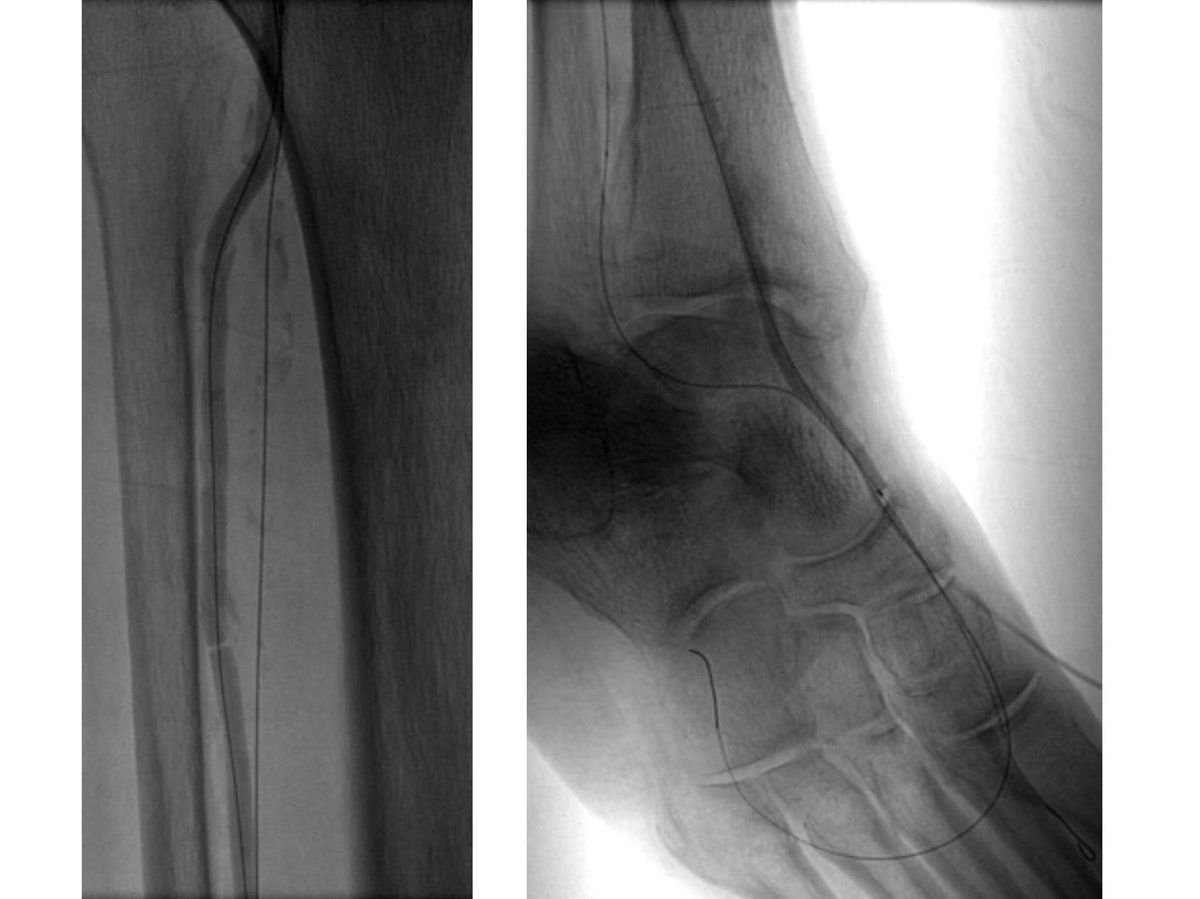

82 yo F with R5 ulcers of 3rd & 4th toes. #IRad can help with infrapopliteal and pedal revascularization to #StopTheChop. #mylegmylife #CLIFighters @SIRspecialists @SIRRFS @CLI_Global @AMPSymposium @pj_rochon

AlexCVIR's tweet image. 82 yo F with R5 ulcers of 3rd & 4th toes. #IRad can help with infrapopliteal and pedal revascularization to #StopTheChop. #mylegmylife #CLIFighters @SIRspecialists @SIRRFS @CLI_Global @AMPSymposium @pj_rochon